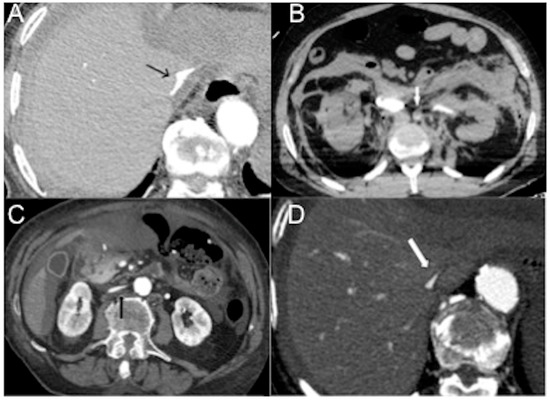

In cardiogenic shock, glandular enhancement can be increased (20 HU greater than the liver and spleen) or decreased in relation to sympathetic overactivity (Figure 8A,B) [25,103,104]. If this self-regulating system of blood flow fails, reduced perfusion of the pancreas ensues, indicating a state of irreversible shock [19]. Hyperenhancement of the adrenals may also be observed in traumatic hypovolemic shock, such as large surface and chemical burns. Peripancreatic fluid in the absence of pancreatitis, pancreatic disease or traumatic injury to the pancreas is secondary to increased pancreatic permeability [19,21].

Figure 8.

CECT and variable pancreatic enhancement. (A) Axial image shows increased pancreatic enhancement (white arrow) and hypoenhancing left kidney (cortical enhancement preserved) (black arrow) in traumatic hemorrhagic shock (multiple thoraco-abdominal gunshot wounds); note flat IVC. (B) Axial image shows decreased pancreatic enhancement in distributive neurogenic shock in a 69-year-old-man with acute basilary artery occlusion. Note non-enhancing spleen and liver heterogeneous enhancement (hot spot sign in left liver). Axial images show splenic hypoenhancement in arterial (C) and venous portal (D) phases (blue circle) in distributive septic shock. Note distended fluid-filled hypotonic stomach (star) with poor thin wall enhancement in arterial phase, but preserved parietography in the delayed phase.

4.2.8. Stomach

Sympathetic activation exerts a predominantly inhibitory effect on gastric muscle and provides a tonic inhibitory influence on mucosal secretion, while at the same time regulating gastrointestinal blood flow via neurally mediated vasoconstriction [105]. We present cases of septic/cardiogenic shock with a massively distended, fluid-filled hypotonic stomach, with poor thin wall enhancement in early and late arterial phases, but preserved parietography in the delayed phase (shock stomach) (Figure 8C,D). To the best of our knowledge, this finding was not described previously in the literature.